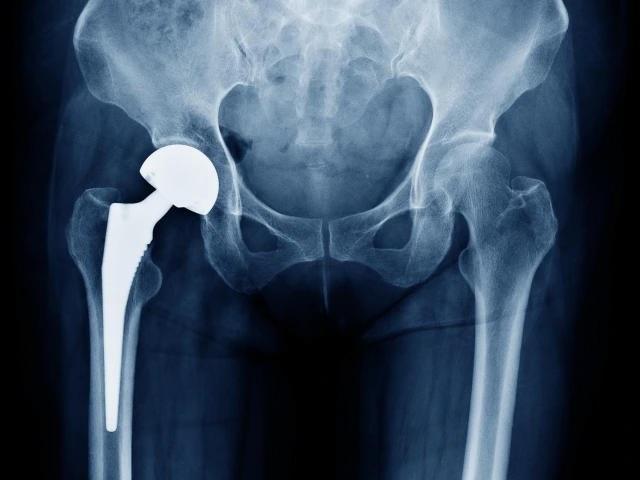

Orthopaedic Surgery Fellowship Programs Sports Medicine Fellowship Sports Medicine Fellowship Hand Fellowship Hand Fellowship Adult Reconstructive Fellowship Adult Reconstructive Fellowship For fellowship information, please contact:Maralyn Enriquezmenriquez@ortho.arizona.edu